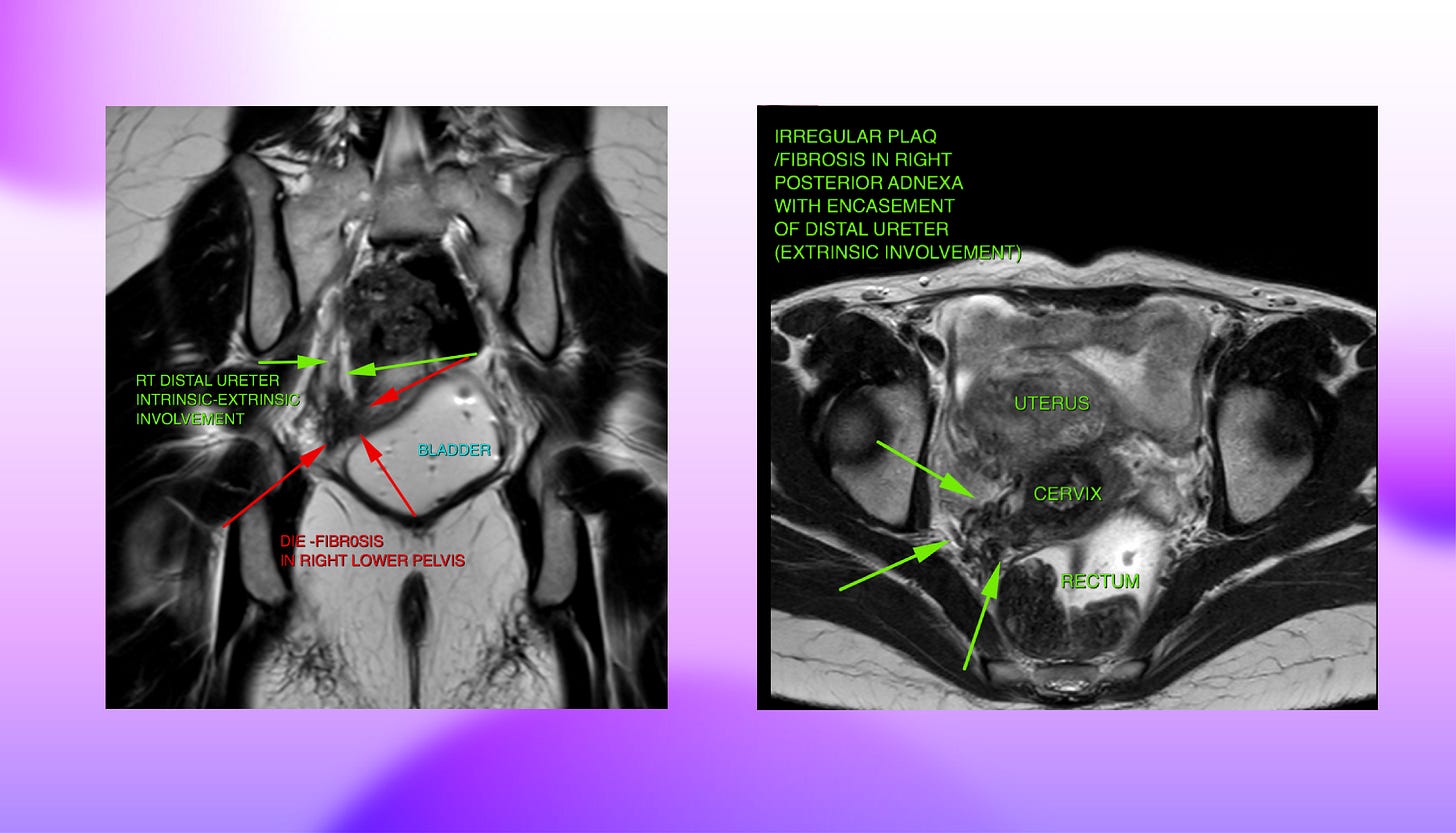

Take the ureters for instance. Observing irregular plaque or fibrosis in the right posterior adnexa in this instance of a T2 weighted axial slice shows an encasement of the distal ureter indicating extrinsic involvement of the ureter. This type of involvement typically results in tethering and angle deviation for the ureter. Whereas another T2 weighted coronal image shows both intrinsic as well as extrinsic involvement of the ureter which might lead to structuring of the lumen and hydroureteronephrosis.